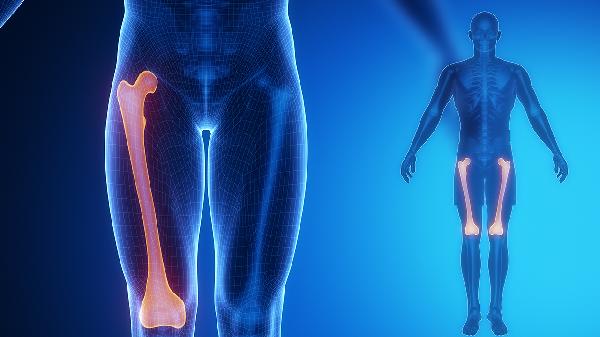

4、腰肌劳损

长期姿势不良或过度负重造成的腰部肌肉慢性损伤,涂抹后可缓解肌肉痉挛。建议同步进行核心肌群锻炼,睡眠时选择硬板床减轻腰椎负荷。